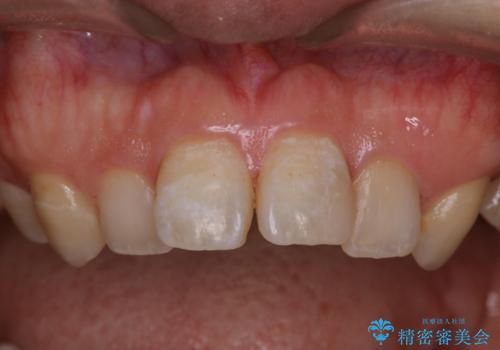

- インビザライン矯正治療の開始前にキレイな状態にしたいとのことでした。PMTC30分コースを行ってからインビザラインの型どりを行いました。

インビザラインの型どり・スキャニング(光学3Dスキャナー「iTero Element」)の前に、プラークや歯石・ステインを除去することで、ご自身本来の歯の状態となるため、綺麗なスキャニングが行えます。より精度のよいマウスピースを作成するために、PMTCを行うことをおすすめしています。